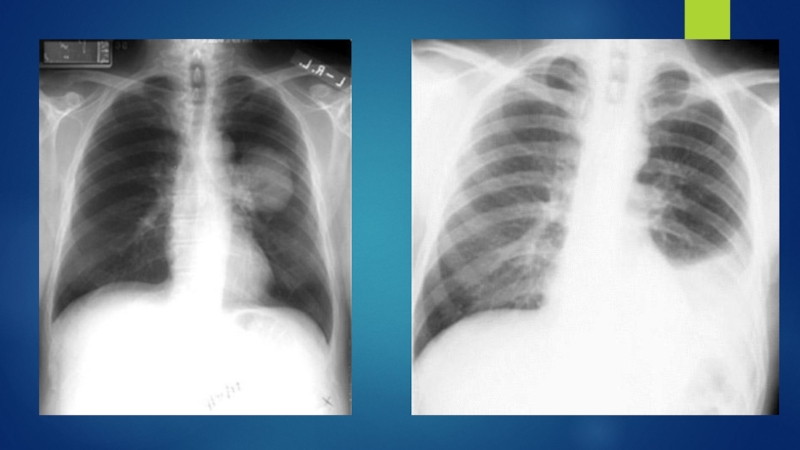

Слайд 20Диагностика

Сбор жалоб, анамнез.

Данные объективного исследования.

Рентгенография:

инфильтрат в легком

расширение средостенья

ателектаз

плевральный выпот

Бронхоскопия

Цитологическое исследование

мокроты

С целью определения степени распространенности процесса производят: КТ органов грудной

полости и верхнего этажа брюшной полости (печень, надпочечники), КТ с контрастированием, МРТ, ПЭТ/КТ, сцинтиграфия костей, КТ или МРТ головного мозга.

ДиагностикаСбор жалоб, анамнез.Данные объективного исследования.Рентгенография:инфильтрат в легкомрасширение средостеньяателектазплевральный выпотБронхоскопияЦитологическое исследование мокротыС целью определения степени распространенности процесса производят: